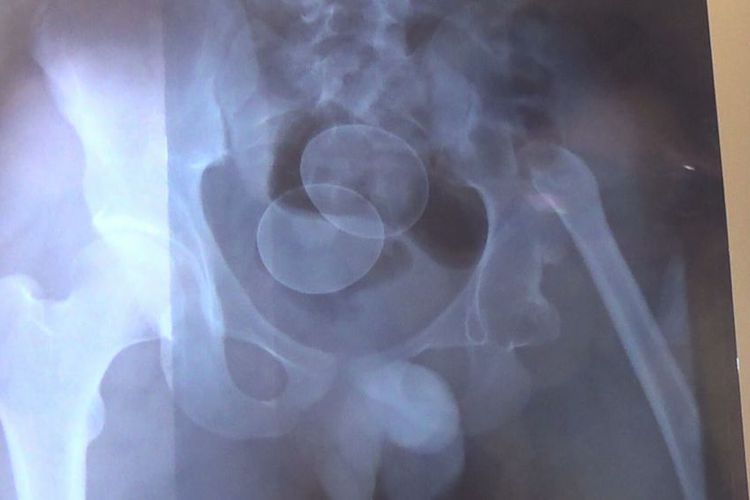

Akmal (14) mengeluarkan telur terakhir di Rumah Sakit Umum Daerah (RSUD) Syech Yusuf Sungguminasa pada pukul 11.00 Wita. Sebelumnya, pihak rumah sakit berhasil mendapatkan foto rontgen letak dua butir telur di dalam tubuh Akmal.

Kini, remaja yang duduk di bangku kelas III SMP ini menjalani perawatan intensif di rumah sakit. Pihak rumah sakit mengungkapkan, dalam dunia medis kasus ini disebut corpus alieniun atau fenomena keberadaan benda asing di dalam tubuh.

"Dalam dunia medis hal ini dikenal dengan corpus alienium atau keberadaan benda asing di dalam tubuh manusia dan sampai sekarang ini kami masih melakukan perawatan terhadap pasien hingga satu pekan," kata dr Ratnah Hafied.(*)